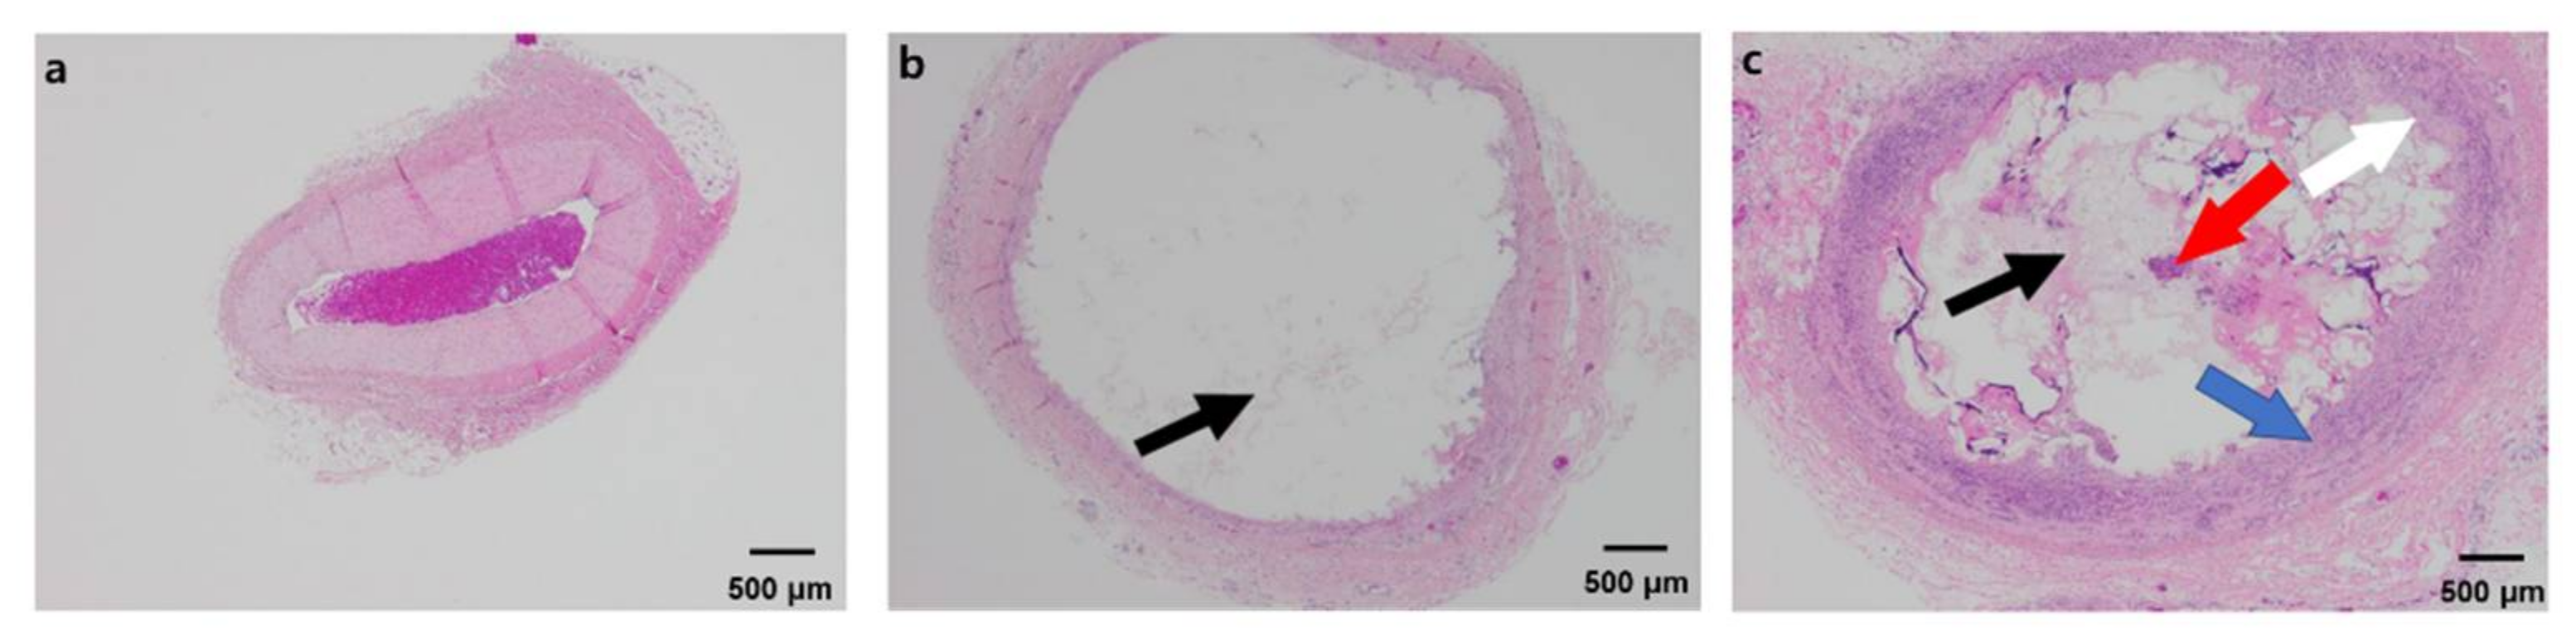

3.4. Histological Study